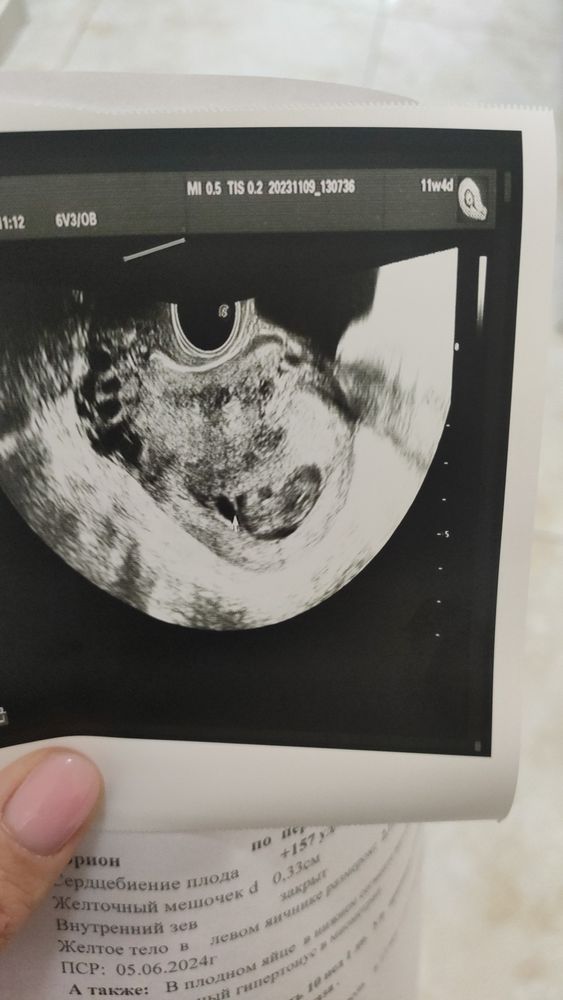

у меня было понятное узи в 10 недель

09.11.2023

Елена Хасап, тоже смотрели вагинально. Советую сходить к другому узисту

Елена Хасап, поищите клинику с более хорошим аппаратом и может хороший узист попадется, потом еще не раз ходить придётся)

Екатерина, я уже 4 УЗИста сменила 😭 прям пздц какой то и беременность непонятная я хоть рада что нет гематомы 🙏 и развивается нормально